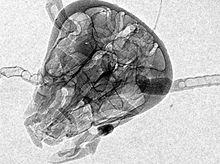

然而,事實上,X射線穿過物體後,不僅強度發生了衰減,其相位也發生了改變。X射線相襯成像利用的就是這一原理,通過紀錄穿過物體的X射線相位的改變,來反映物體內部電子密度的分布,也即我們常說的物體內部結構。

1、 適合於弱吸收物質成像。所謂弱吸收物質,即對X射線衰減很小的物質,包括高分子材料、生物體組織,傳統X射線成像對其顯示很不清晰。而這類物質對X射線的相位改變卻相對較大,因此相襯成像方法能有效顯示其內部結構。

X射線相襯成像在上個世紀90年代發展起來,主要有干涉法、衍射增強法、類同軸法和光柵法。採用的光源有微焦點光源和同步輻射光源。世界各國均在展開相關研究,主要有澳大利亞、日本、美國、中國和歐洲國家。在澳大利亞,基於微焦點光源的類同軸法已經初步商業化。在國內,清華大學工程物理系、中科院高能所、首都醫科大學等單位均在進行研究工作。相襯成像主要用於樣品結構、生物化學過程的研究,未來將有望套用於臨床醫學。